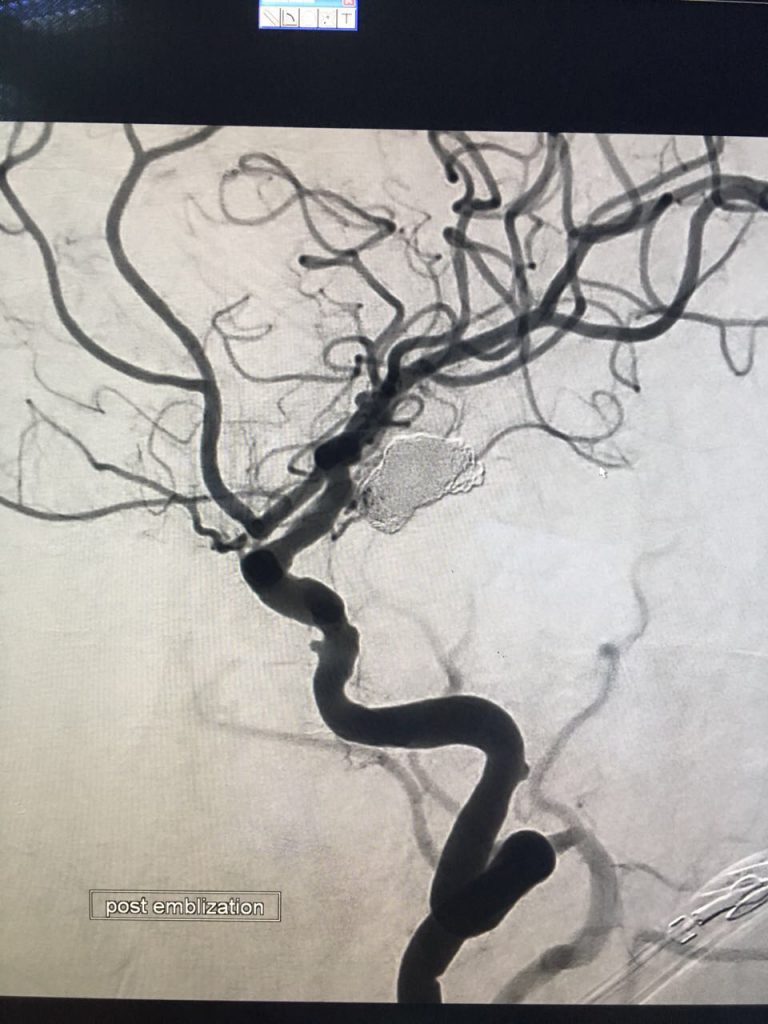

نجح فريق طبي بمستشفى الملك فهد المركزي بجازان بقيادة استشاري الأشعة التداخلية وقسطرة الأوعية الدموية للدماغ الدكتور أحمد النجدي في علاج حالة حرجة لمريضة خمسينية تعاني من نزيف حاد بالدماغ، وذلك بقسطرة الشرايين وإقفال مكان النزيف في الدماغ تحت الأشعة السينية، والتي استغرقت ما يقارب الثلاث ساعات و النصف ، وقد تكللت العملية بالنجاح ولله الحمد.

ويعتبر هذا التخصص النادر مكملاً لوحدة الأشعة التداخلية وقسطرة الأوعية الدموية بالمستشفى والذي يساهم في علاج الحالات دون الحاجة إلى فتح جراحي ، كما يمكن من خلالها علاج الجلطات وتشوهات الشرايين والأوردة بالدماغ حيث تحرص إدارة المستشفى على تقديم خدمات طبية متقدمة تساهم في تقليل نسبة إحالة الحالات المرضية للعلاج خارج المنطقة.